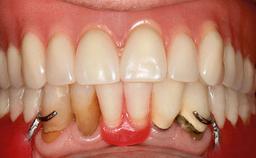

Four Immediately Loaded Mini-Implants Supporting a Mandibular Overdenture

A 74-year-old male patient, a non-smoker, who had been wearing complete dentures for more than 30 years, presented to our clinic complaining about discomfort in connection with his lower denture. The patient suffered from asthma and had a history of cardiac disease and blood pressure disorders. All conditions were medically controlled and stable. The clinical inspection of the oral cavity revealed an ill-fitting complete mandibular denture. The patient expressed the wish for his lower denture to “stop moving when chewing, swallowing, and speaking.” He reported having heard about dental implants and asked whether these could help in “fixing” his lower denture, but also requested non-invasive treatment. The mucosa presented healthy and was free of defects such as pressure sores. An band of keratinized mucosa approximately 2 mm wide was visible. The patient’s mucosal biotype was medium thick to thin.

# of Implants 4

Type of Implants One-Piece|Reduced-Diameter